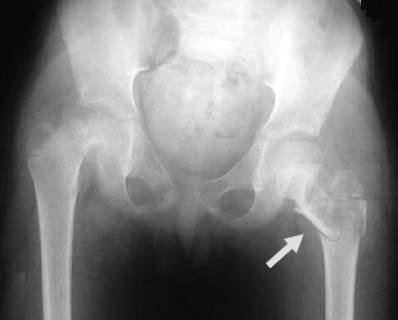

• Radiología pelvis

• Lesión osteolítica del femur izquierdo, con fractura patológica subcapital, en relación con metástasis oseas.